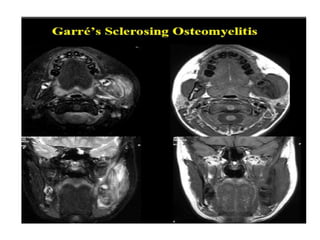

O documento fornece informações sobre como realizar exames de ressonância magnética do pescoço e angiorressonância magnética das carótidas, incluindo parâmetros, programação, anatomia, exames estruturais e funcionais, dicas e protocolos.